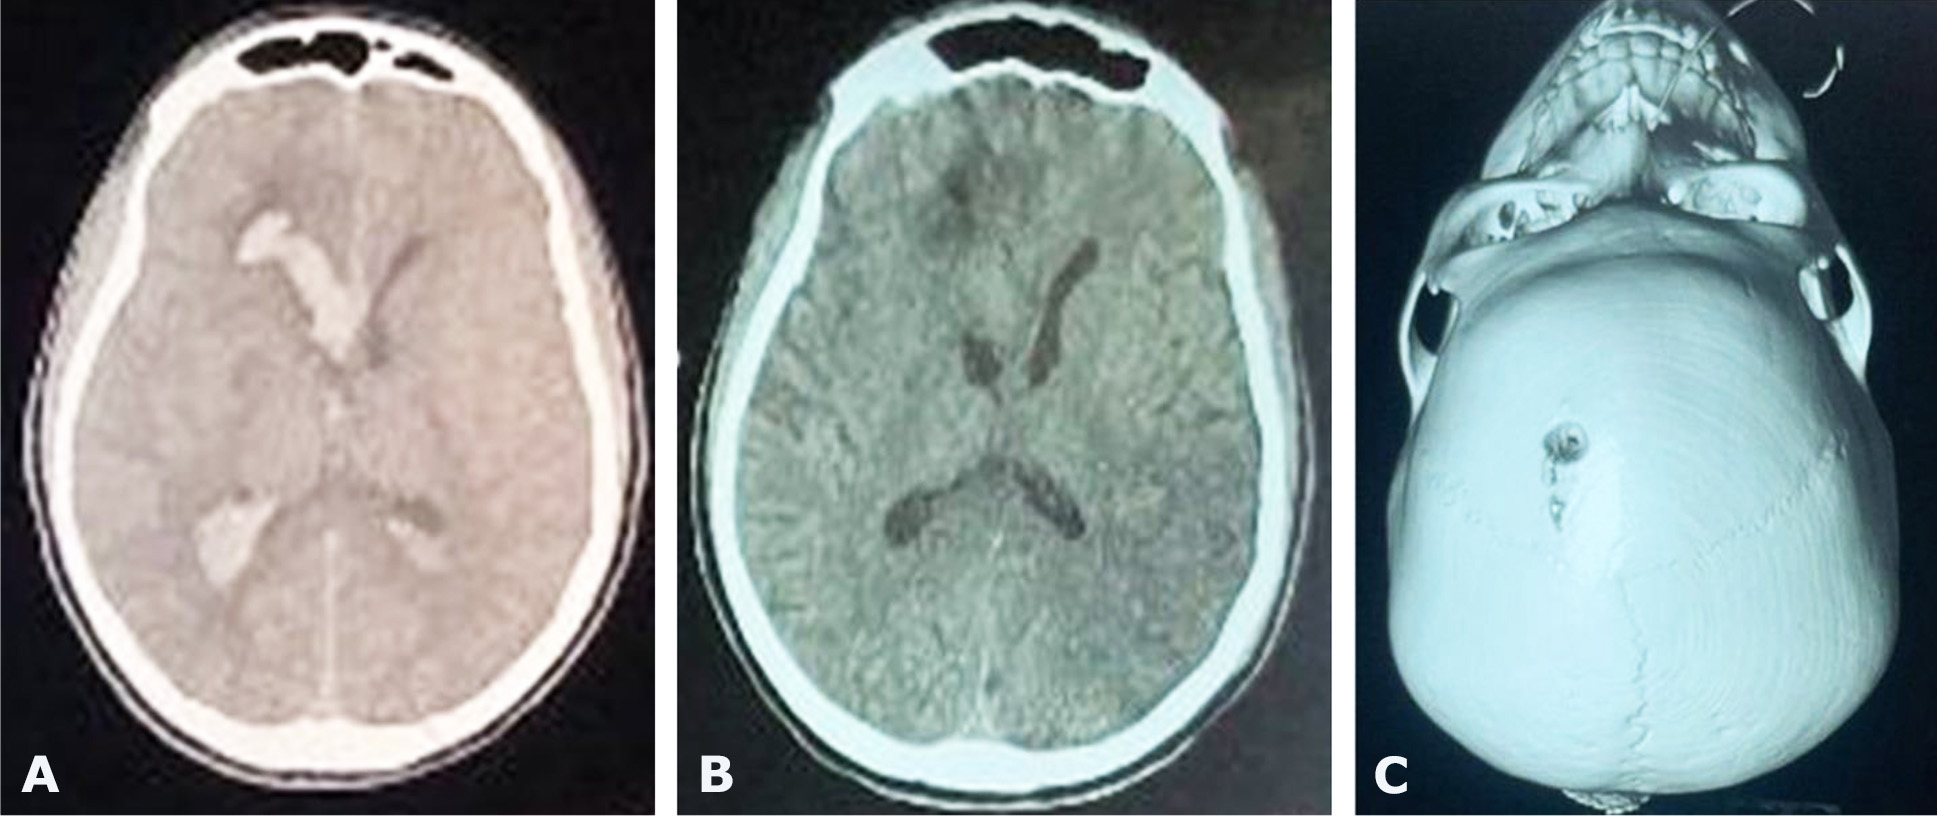

During the study period, a total of 63 patients were admitted for spontaneous ICH and IVH was associated in 24 (38.1%) patients. Among them, EVDs were placed in 17 patients. The mean age was 49 years with range of 27 to 66 years. There were 11 males and 6 females. The main risk factors of stroke were hypertension in 13 patients and diabetes in 7 patients. The initial GCS was between 5 and 8. Unilateral pupillary dilatation was found in 8 patients (Table 1). EVD was placed in frontal horn in the lateral ventricle in all cases (Fig. 1, 2) and continuous CSF drainage was indicated leading to ventricle size and blood clot removal (Fig. 2, 3). The duration of EVD was 1 to 8 days. Four (23.5%) patients experienced infection as a complication. The short-term mortality rate was 70.5 % at 30 days including 8 males and 4 females with a mean age of 53 years. The functional outcomes were poor in 4 patients with mRS sore of 4 and 5 (Table 2). The independent predictor factors for 30-day mortality (Table 3) were poor GCS (p=0.319), mydriasis (p=0.245) and poor Graeb score (p=0.004).

Fig. 1. Preoperative CT scan showing IVH (A), postoperative CT scan showing intraventricular location of the catheter tip (B) and photograph of Patient with EVD in-situ ICU (C)